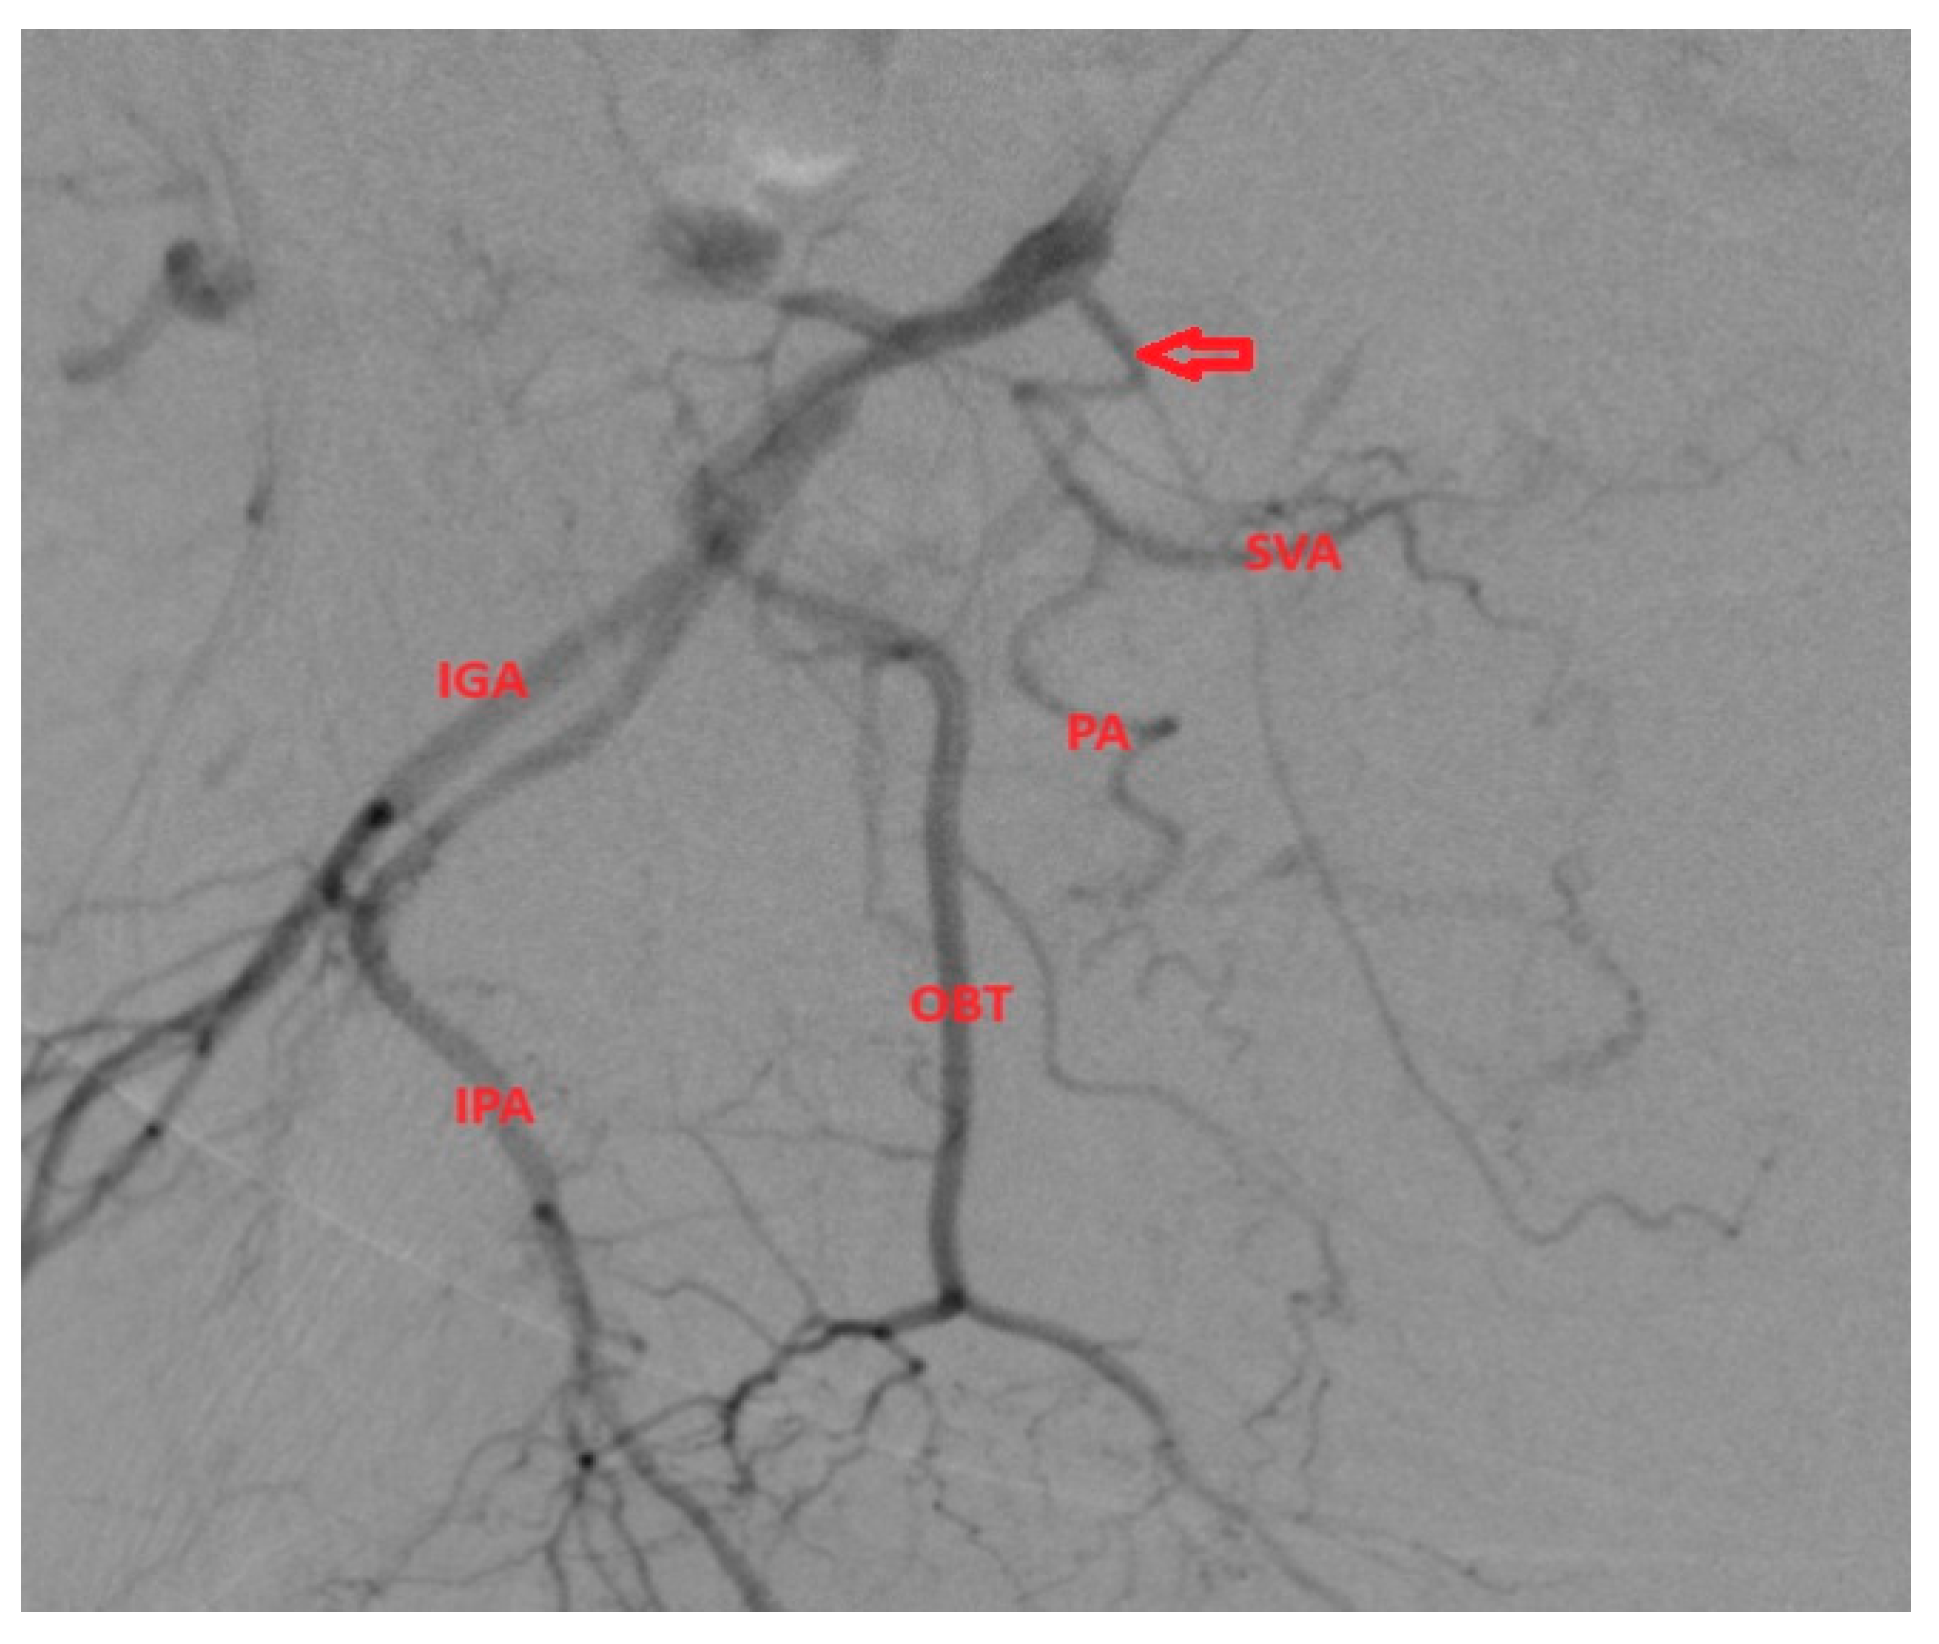

- After we identified the four main branches (superior gluteal artery, inferior gluteal artery, obturator artery, internal pudendal artery), we searched for the PA artery, which usually has a characteristic corkscrew aspect and parallel trajectory with the IPA.

- Type of internal iliac artery (IIA) branching pattern from Yamaki classification which helps to identify possible origins of the PA [3].

3.1.3. PA with Origin from SVA